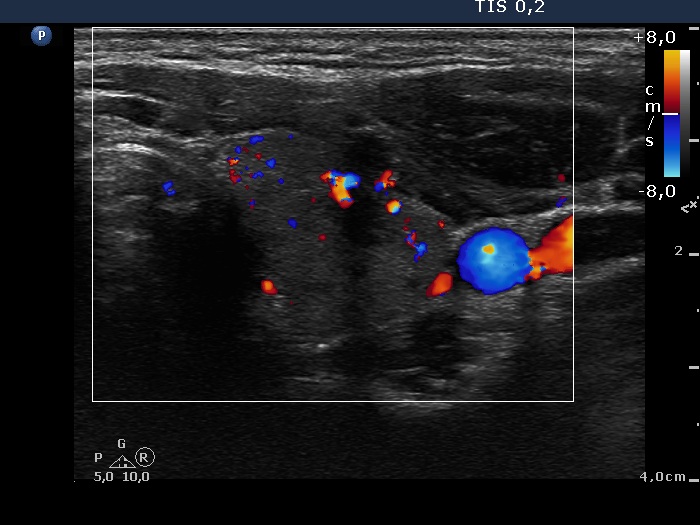

Discrete lesion or nodule in Hashimoto's thyroiditis - case 10 (95) (ultrasonographic picture 9)

Left lobe, transverse scan, color Doppler mode. The hypoechogenic area presents increased intralesional vascularization which is relatively unusual in the event of subacute thyroiditis.